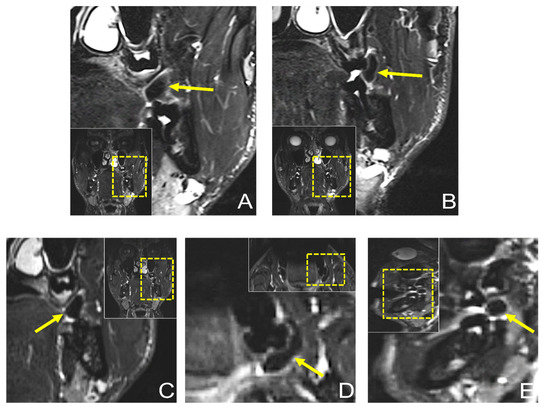

Dental MRI showed a well-demarcated lesion with a maximum extension of 21.3 × 5.6 mm (axial), 13 × 8.6 mm (coronal), and 10.1 × 9.8 mm (sagittal) on a T2 STIR protocol, with homogenous low signal intensity in the central area of the lesion, while the peripheral area showed a high signal intensity. The lesion originated from the planum buccale and did not infiltrate adjacent structures, with a displacement of the second upper molar (Figure 4). The DESS protocol revealed the same hypointense lesion with lower resolution and image quality compared with the STIR protocol (Figure 5). Thus, the radiological findings excluded any further involvement in the head and neck area, the presence of a lipoma, or other space-occupying pathologies, and provided the precise localization and extension of the suspected fibromatous lesion.

Figure 5.

Preoperative MRI of the same lesion using 3D double-echo steady-state (3D-DESS) imaging protocol. (A) Axial, (B) coronal, and (C) sagittal reconstructions visualizing a well-demarcated lesion with a maximum extension of 21.3 × 5.6 mm (axial), 13 × 8.6 mm (coronal), and 10.1 × 9.8 mm (sagittal). For orientation, the dotted rectangles in the corner show the enlarged area. The MR image reconstructions seem to have a slightly lower resolution due to the larger scale along the slice direction.